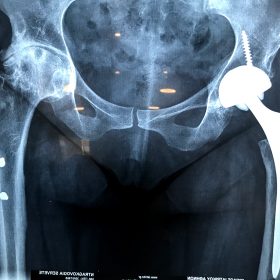

Διάγνωση- Σταδιοποίηση

Διακρίνονται σε 4 στάδια.

Στάδιο Ι. Στένωση του μεσαθριου διαστήματος

Στάδιο ΙΙ. Σκλήρυνση του υποκύμενου χόνδρου

Στάδιο ΙΙΙ. Σκλήρυνση του υπερκείμενου χόνδρου, καταστροφή του υποχόνδρινου οστούν, σχηματισμός οστεόφυτων, οίδημα αρθρώσεως και βραδυνός πόνος

Στάδιο IV. Οστική καθίζηση, καταστροφή μαλακών μορίων μυϊκών ομάδων, υπεξάρθρημα της αρθρώσεως και αλλαγή του μηχανικού άξονα